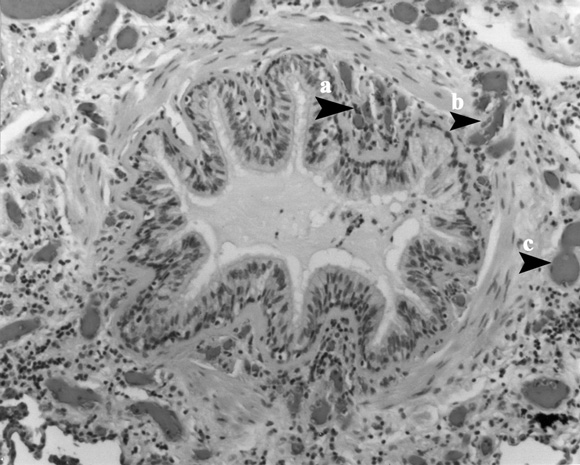

Vascular arrangement in the airway wall of an adult with asthma

The vessels in the submucosa (a) are smaller than the vessels in the adventitia (c), and the vessels that pass through the muscle layer (b) connect them. These two sets of vessels are perfused in series, providing a basis for a difference in the nature of the inflammatory reaction in the submucosa and lumen compared with the peribronchiolar space.